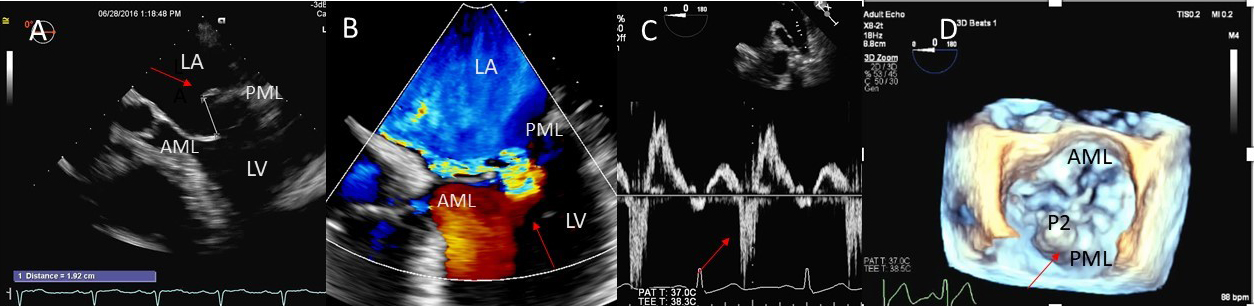

These criteria are generally more reliable in central jets. Pulmonary artery systolic pressure, mitral inflow E wave velocity and pulmonary vein flow pattern are other helpful parameters. Systolic pulmonary vein reversal (Fig. 1) is highly specific for severe MR but is not very sensitive. Discrepancy may occur between MR ERO and RV in mitral valve prolapse in early stages of MR where non holosystolic MR jet duration and hence regurgitant volume are smaller than the PISA derived EROA which does not account for the duration of MR jet. 2D vena contracta width may be unreliable in eccentric jets, however direct measurement of regurgitant orifice can be done using 3D color Doppler vena contracta area which may allow better quantitation of MR in central as well as eccentric MR jets [5] as well as in patients with multiple MR jets in whom PISA quantitation by adding multiple jets has not be validated and in whom continuity equation cannot be performed [6].

Fig. 1.Degenerative MR due to Flail posterior mitral valve leaflet. (A) TEE 4 chamber view showing a flail posterior mitral valve resulting in a severe anteriorly directed mitral regurgitation jet. LA, left atrium; LV, left ventricle; AML, anterior mitral leaflet; PML, posterior mitral leaflet. (B) TEE 4 chamber view color Doppler showing anteriorly directed mitral regurgitation with PISA (red arrow). AML, anterior mitral leaflet; AV, aortic valve. (C) Pulsed wave Doppler showing left upper pulmonary vein systolic flow reversal. (D) 3D TEE enface view of the mitral valve from the atrial perspective demonstrating P2 flail scallop with torn chordae. Aortic valve is a 9 o’clock position. AML, anterior mitral leaflet; PML, posterior mitral leaflet.